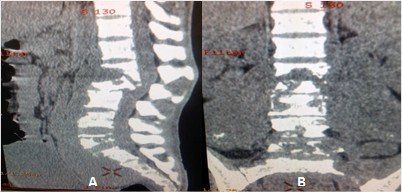

Los cortes sagital y coronal muestran el grado de destrucción vertebral lumbosacra, deformidad y angulación raquídea, asociados a ligera compresión medular, así como el engrosamiento y calcificaciones de los músculos psoas bilateralmente. (Fig. 2).